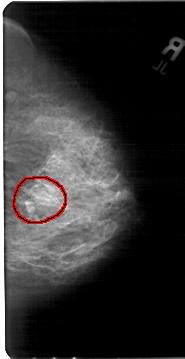

A_1397_1.RIGHT_MLO

RIGHT_MLO LINES 5491 PIXELS_PER_LINE 2941 BITS_PER_PIXEL 12 RESOLUTION 43.5 OVERLAY

FILE: A_1397_1.RIGHT_MLO.OVERLAY

TOTAL_ABNORMALITIES 1

ABNORMALITY 1

LESION_TYPE MASS SHAPE LOBULATED MARGINS OBSCURED

ASSESSMENT 4

SUBTLETY 3

PATHOLOGY BENIGN

TOTAL_OUTLINES 1

BOUNDARY